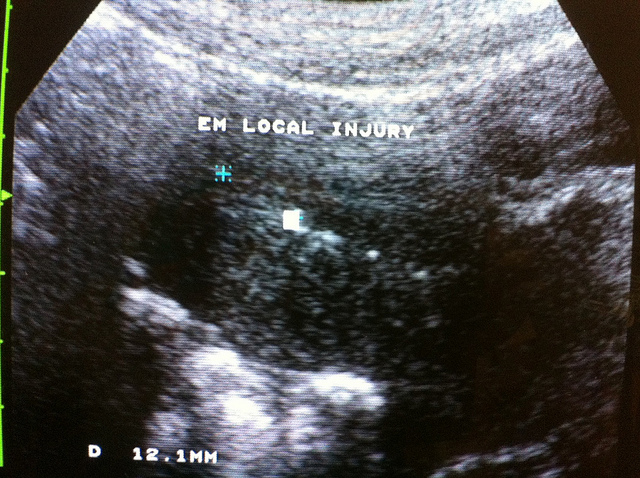

我們每個人的體內都有殺手細胞,工作職責是要殺死癌細胞,和外來病毒,細菌的入侵,但一個人如果 殺手細胞過高,就會有可能殺死胚胎!!殺手細胞,和腫瘤壞死因子 -α(TNF- α ),有很大的關連性,如果 TNF-α過高,會激活〝殺手〞細胞,也就是說可以唆使〝殺手〞 細胞攻擊胚胎,胎盤,導致胎盤,細胞壞死,這些壞死的細胞變成碎片,引來免疫系統的吞噬細胞(macrop hage),聚集在子宮,產生更嚴重的發炎反應,因此就流產了,因此,有 一類習慣性流產的病人,就是因為過多的殺手細胞,而引起的,(當然這比率不高),博元婦產科不孕症試管嬰兒中心,在2007 年台灣生殖醫學會年會上報告一個病例,病人本身有類風濕性關節炎 (R.A),病人30 多歲,在去年有一次不明原因流產,9週的時候,進行流產手術,經本院向衛生署申請公文把檢體寄送到* 美國*,進行特殊的免疫染色細胞分析,赫然發現她子宮裡面有超乎尋常的 ,過多大量的殺手細胞,至少在 400倍的顯微鏡底下,平均有*28.2*個殺手細胞,這是去年 2006年6月,7月的事情,*美國*的醫師的報告!!剛剛好在 去年2006年 11月,台灣衛生署核准一種腫瘤壞死因子的抑制劑,叫做Humira ,這個藥甫一核准上市,她就在風濕免疫科醫師的同意下, 打這種針,完成療程之後,她在今年,年初2007年1月,找博元婦產科進行子宮內膜切片研究分析,子宮內 的殺手細胞是否獲得控制?本院執行子宮內膜切片寄送去美國化驗, 也是一種特殊的免疫染色分析,這時候子宮內的殺手細胞降到幾乎看 不到,每400倍的顯微鏡底下平均才*1.3* 個殺手細胞,這樣的數量是不至於引起流產的,我在幫她做內膜切片 的時候,剛好她要出國旅遊,因為那時候是月經的第26天, 我根據她的月經週期,幫她推算她在國外大約哪一天會排卵, 建議她們在那幾天行房,在她的排卵日以前, 我們已經收到她打針之後的子宮病理報告,確定子宮適合胚胎的著床 ,很幸運,她自然同房一次就中獎,目前已懷孕成功,約26週,我們恭喜這一位本身有類風濕性關節炎,可是她在去年 6月類風濕性關節炎已經緩解了,到現在還沒有復發,她的子宮因為 有大量的殺手細胞而流產,經過Humira治療,把殺手細胞數目降到從28.2個降到 1.3個,就自然懷孕成功,這一種使用TNF- α抑制劑,來治療習慣性流產的成功案例,*在2001年,2003**年分別只有一個病例報告*,我們在這裡恭喜這一位曾經歷經流產 ,又有類風濕性關節炎的病患,使用Humira降低子宮裡面過多 的殺手細胞,跟自然懷孕成功,恭禧!恭禧!